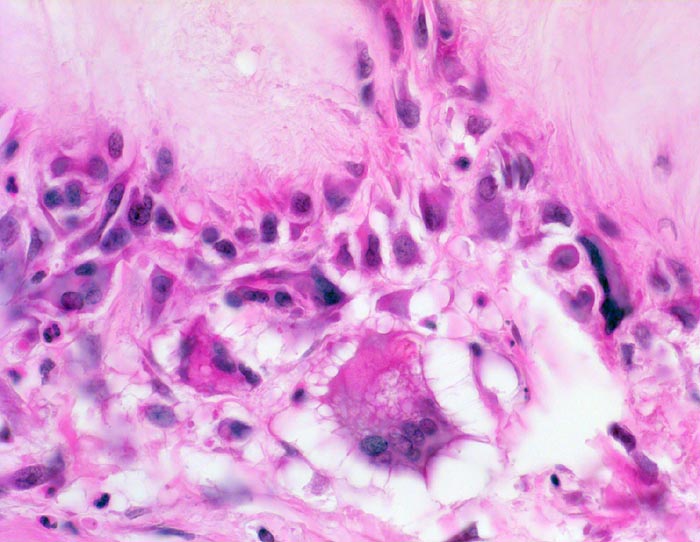

• Kollagenes Bindegewebe mit Tophus bestehend aus wolkiger eosinophiler Matrix mit herdförmig erkennbaren nadelförmigen Strukturen (Uratkristalle).

• Die Ablagerungen sind umgeben von mehrkernigen Fremdkörperriesenzellen, Makrophagen und wenigen neutrophilen Granulozyten.